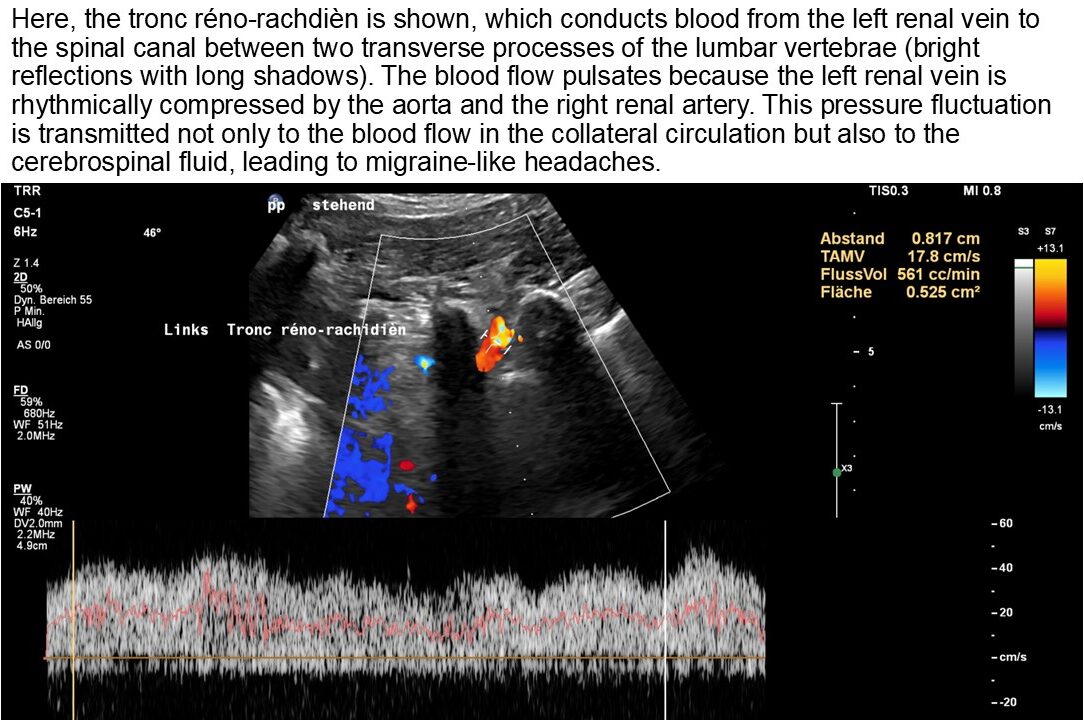

A collateral circulation branches off from the left renal vein to the spinal canal—a so-called tronc réno-rachidièn—which feeds 148 ml/min into the epidural plexus in a horizontal body position. When standing, the perfusion of the vessel increases to 531 ml/min.

This contributes to an increase in pressure in the spinal canal and subsequently intracranially, which would explain headaches and, in some cases, neurological deficits in the cranial nerves (visual disturbances, speech disorders, bulbar motility disorder). The drastic increase in spinal and thus cerebral congestion when standing after eating. This corresponds exactly with the patient’s description of unbearable headaches after every meal.